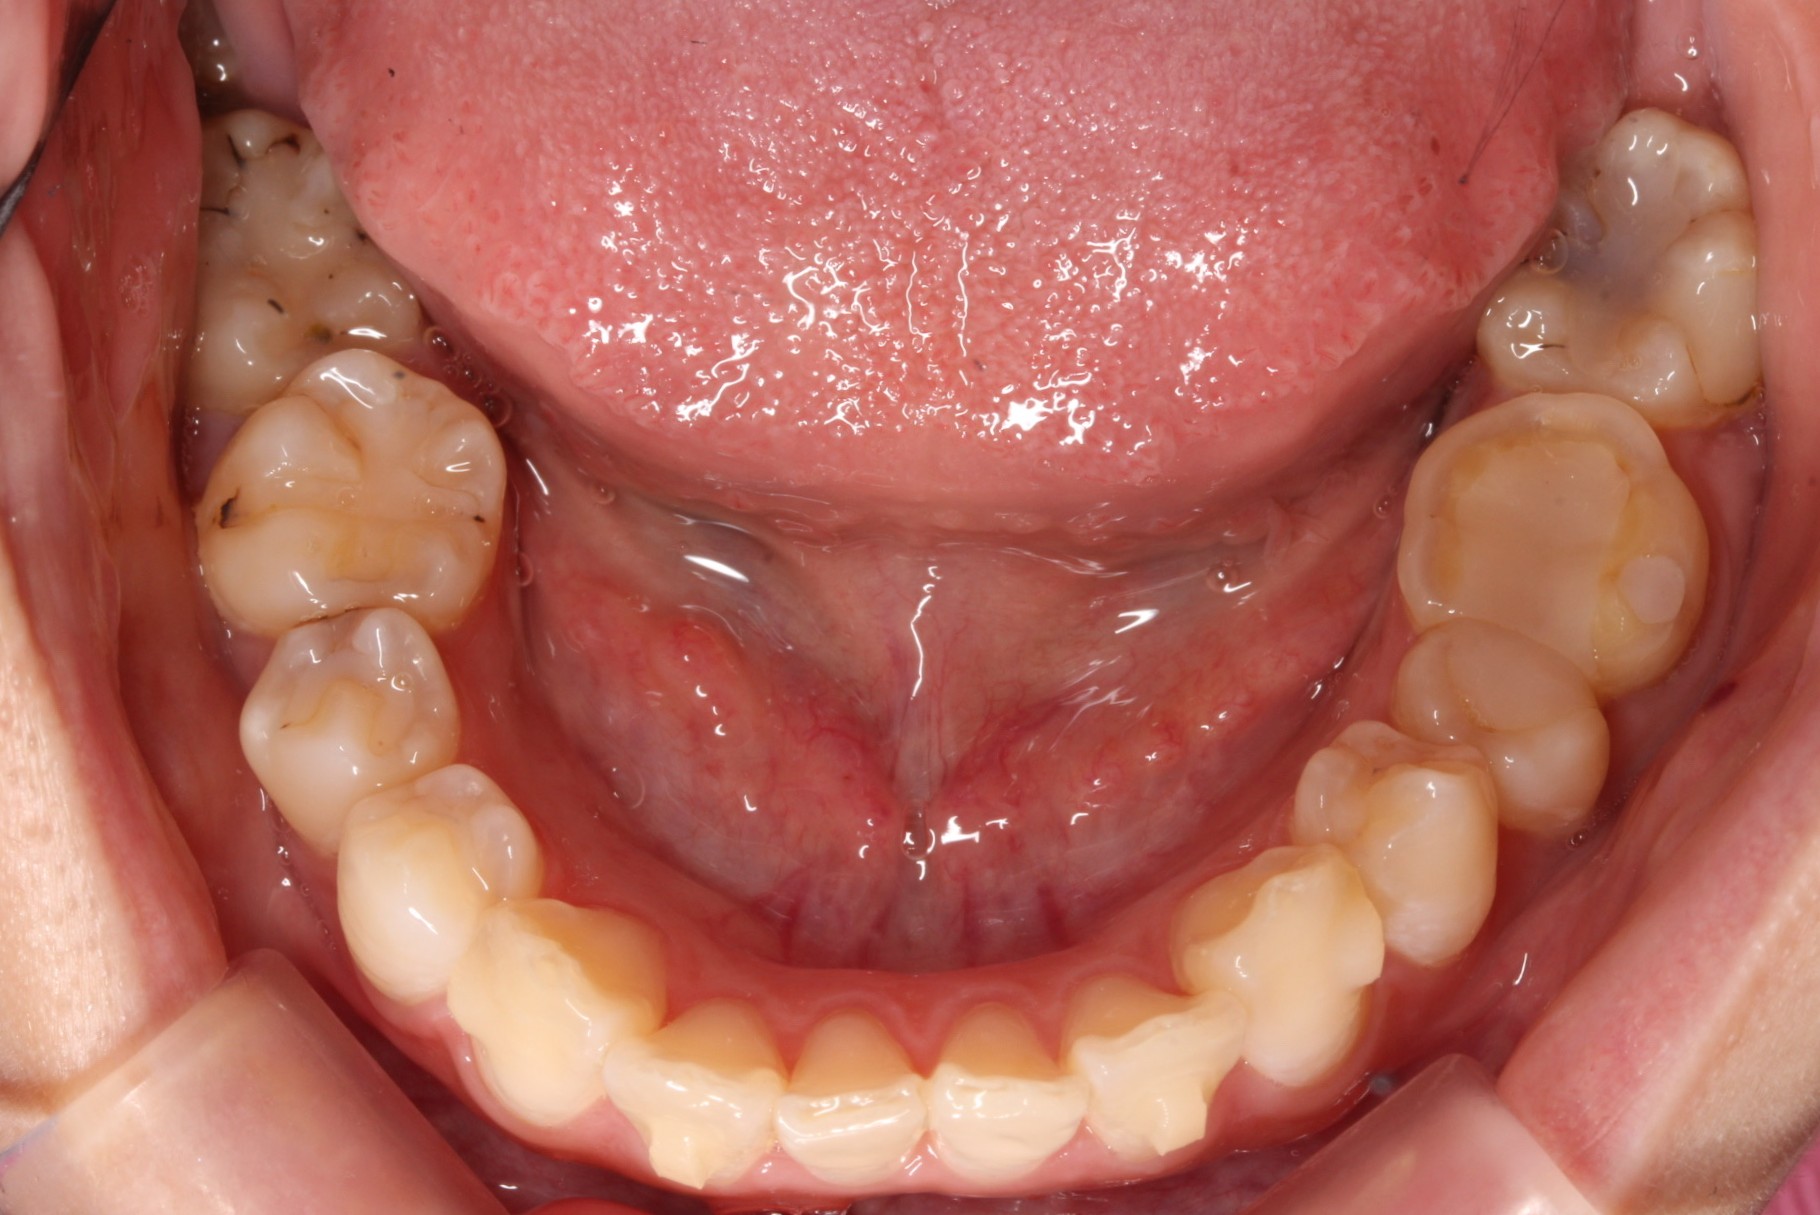

矯正術前:下顎

矯正術後:下顎